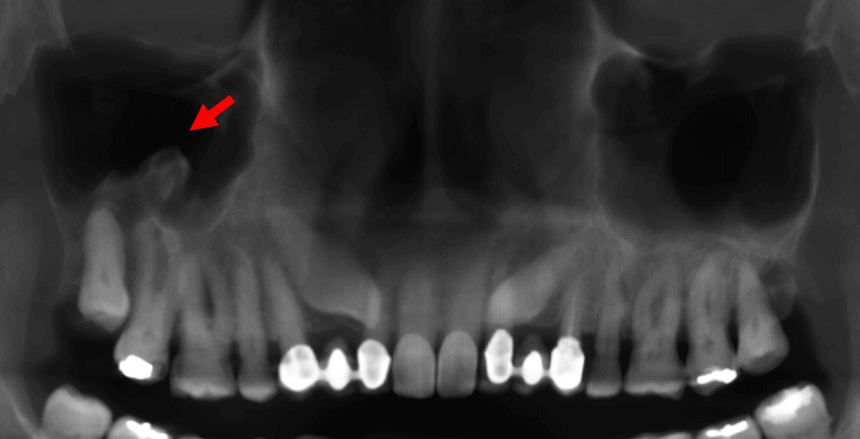

Fig.2

En cortes coronales (Fig.2) se observa que dicha estructura radiopaca en el interior del seno maxilar derecho tiene densidad ósea (flechas rojas) y es dependiente de la pared basal y lateral. SE observa también que se proyecta en sentido cefálico. Nótese la lesión osteolítica de aparente origen odontogénico de forma controlateral en relación con el molar, la cual condiciona el engrosamiento de la mucosa antral del seno maxilar izquierdo (flecha azul).